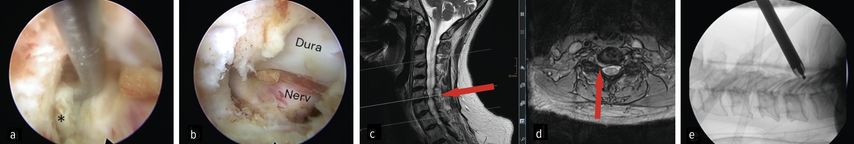

Der zervikale Bandscheibenvorfall und die Neuroforamenstenose sind weitere klinische Einsatzgebiete der spinalen Endoskopie. Insbesondere die posteriore endoskopische Foraminotomie und Diskektomien nehmen an Bedeutung zu. Die Sicherheit des Verfahrens wird durch effektive Hämostase und klare Sicht dank kontinuierlicher Irrigation unterstützt. Ruetten et al. konnten in einer RCT an 175 Patienten zeigen, dass die posteriore endoskopische Foraminotomie im Vergleich zur ACDF ein gleichwertiges neurologisches Ergebnis erzielt, bei erhaltener Beweglichkeit des operierten Segmentes.28 In unserer Abteilung wird die Technik bei ossären Neuroforamenstenosen und intraforaminären Bandscheibenvorfällen gewählt. Abbildung 7 zeigt einen intraforaminärer Diskusprolaps C6/7 rechts im präoperativen MRI (c, d), die endoskopische Sicht auf Duralsack, Nervenwurzel C7 rechts und Sequester (Stern, a) in der Nervenachsel (a) sowie die Ansicht auf die dekomprimierte Wurzel (b). Des Weiteren zeigt sie eine intraoperative Positionskontrolle während der medialen Facettenresektion C6/7 (e).